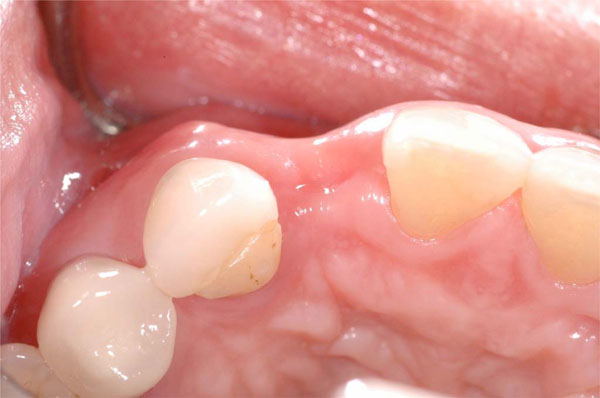

Extraction site defect 6 months after tooth removal without ridge preservation. Note buccal depression and loss of vertical height at site #10.

Esthetic defect caused by tooth loss without ridge preservation requiring guided bone regeneration to adequately place an implant at the #10 site for an acceptable outcome (occlusal view).

As previously mentioned, the extraction of a tooth frequently led to a deficiency in ridge width and height of the alveolar crest, which affected the optimal placement of an implant (Fig. 2). Allegrini et al. reported that ridge preservation decreased early alveolar ridge width loss after tooth extraction. Bone replacement grafts for ridge preservation are defined by the American Dental Association as osseous autograft, allograft or non-osseous graft placed in an extraction site at the time of extraction to preserve ridge integrity. The success of bone grafting procedures is ultimately dependent upon revascularization and remodeling of the grafted bone into vital, load bearing bone. Autografts and other bone substitutes, allografts, xenografts, synthetic biomaterials and osteoactive agents help restore alveolar bone loss or maintain dental alveolar bone after extraction, supporting optimal placement of dental implants [17].